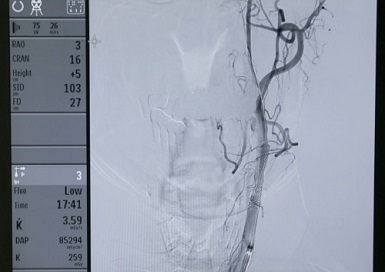

뉴로인터벤션(Neuro-intervention)이란 첨단 투시 장비를 이용해 피부에 작은 구멍만을 내고 혈관을 통해 들어가 막힌 혈관을 뚫어주고 터진 혈관을 막아주는 치료법이다.

영상만으로 복잡하고 어려운 뇌혈관을 치료해야 하는 만큼 의료진의 경험과 노하우가 중요한데...

EBS 명의 <수술 없이 뇌혈관을 살린다! - 뉴로인터벤션> 편에서는 영상의학과 김동준 교수와 함께 뉴로인터벤션 치료법과 시술법을 알아본다.

김동준 교수는 이 문제를 해결하기 위해 경동맥에 스텐트를 삽입하는 시술을 시행했다.

외과적 수술인 경동맥 내막절제술을 시행할 수도 있지만 나이와 증상 유무를 고려해 뇌경색 예방을 위한 치료 목적으로 뉴로인터벤션을 선택했다.